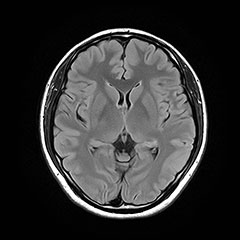

MRI

脳卒中、脳腫瘍、脳萎縮、白室病変、脳室拡大

日本脳ドック学会の推奨する検査内容となります。 頭部MRI検査(T1WI, T2WI, FLAIR, T2*)、頭部MRA検査、頚動脈MRA検査、血液検査、尿検査、心電図検査を行います。